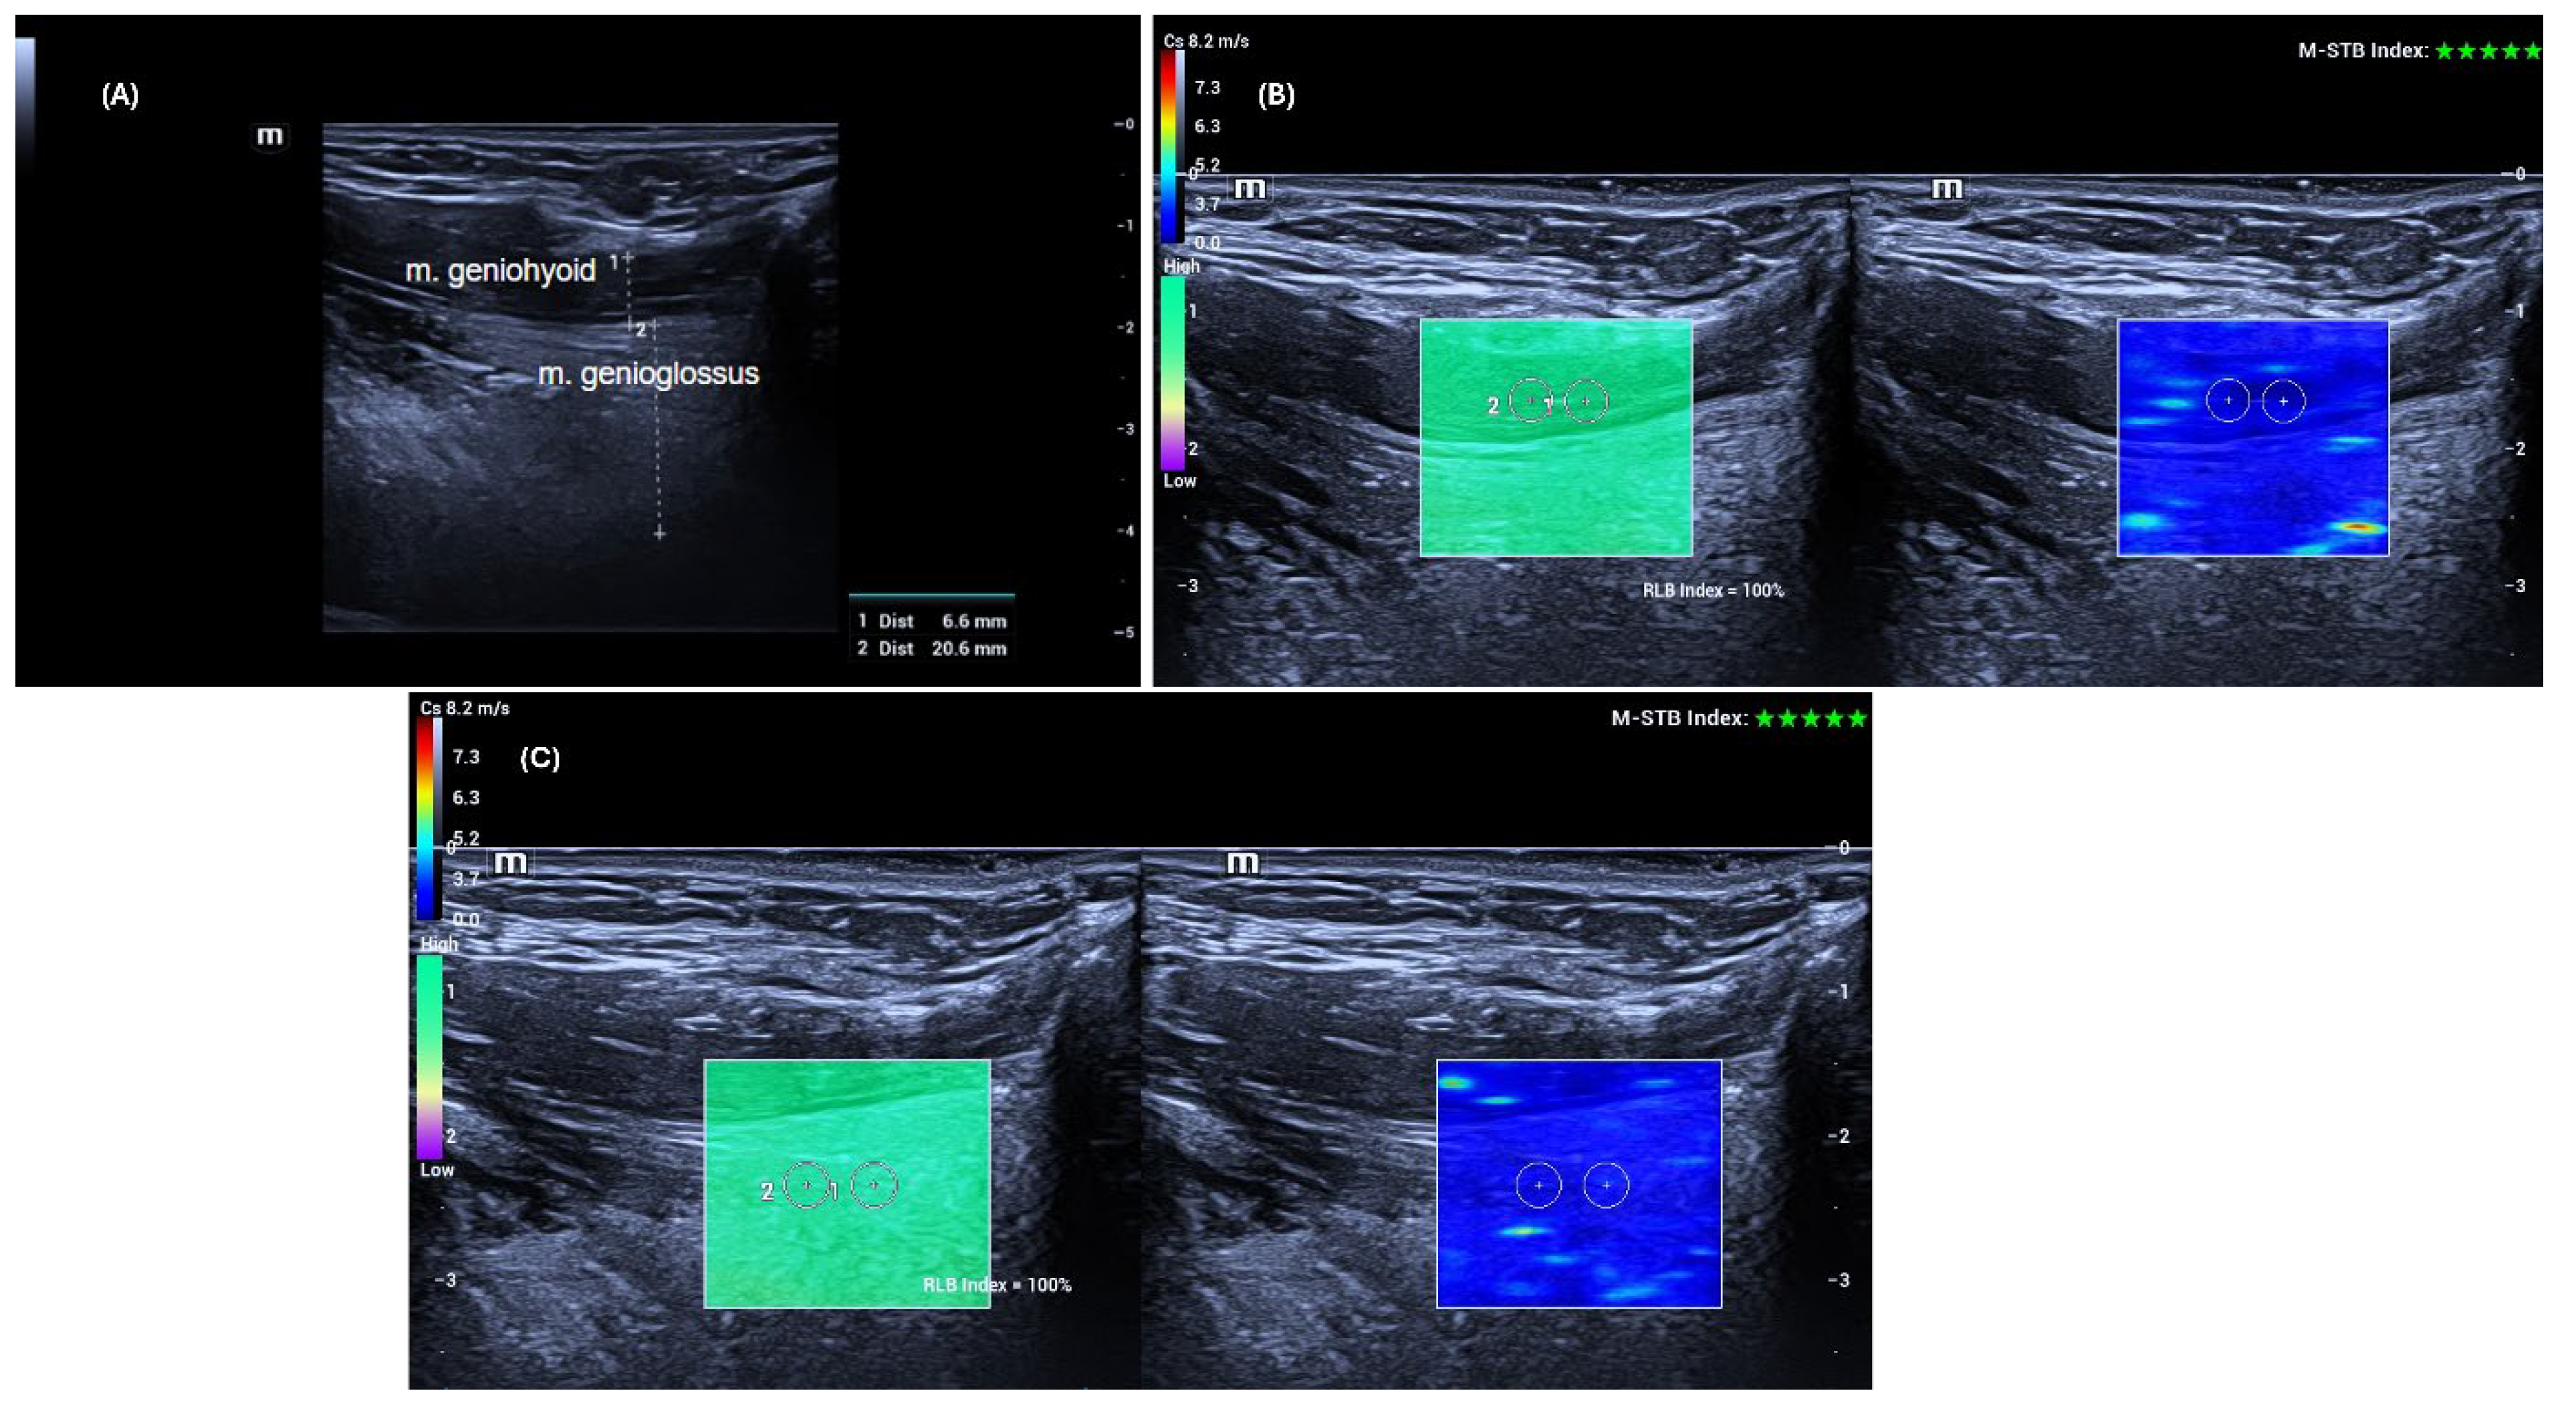

The ultrasonographic and shear wave elastography examinations of the genioglossus and geniohyoid muscles were performed according to previously described protocols in the literature [

12]. Patients were positioned supine with the head in slight extension. They were instructed to keep the tongue free in the mouth without touching the palate or retracting it.

To adequately visualize the target muscles, the transducer was first placed transversely in the midline of the submental region. Once the muscles were identified, the transducer was rotated to a longitudinal position, and thickness and elastography measurements of the right and left GG and GH muscles were performed sequentially. Care was taken to position the probe perpendicular to the skin without applying pressure.

Ultrasound examinations were performed on the same day before the polysomnography. Muscle thickness was measured using grayscale B-mode ultrasonography (US) as the anteroposterior distance between the superficial (anterior) and deep (posterior) fasciae of the muscle, after which shear wave elastography (SWE) measurements were conducted using the same high-frequency linear transducer, without changing the probe. Muscle elasticity was assessed at five different points using a 3 mm × 3 mm region of interest (ROI) placed away from fasciae and bony structures, and the results were recorded in meters per second (m/s). The mean value obtained from the five measurements was considered the stiffness value of the muscles.

All data were obtained using the SWE mode of the same US device (Mindray Resona I9, Shenzhen, China). Measurements were performed with a high-frequency linear transducer (L14-3 Ws) by a radiologist with 14 years of experience. Advanced technologies provided by the manufacturer supported the accuracy and stability of the measurements. The “Motion Stability” (M-STB) function allowed real-time monitoring of motion in the target area, and measurements were only recorded when a 4–5-star rating and green indicator were present. Additionally, image quality was assessed using the “Reliability Map” (RLB MAP) function, and measurements were taken only in areas with a reliability index of ≥90%. In cases of low signal quality or no signal, the measurement was considered invalid and repeated. Additionally, to increase measurement reliability, the interquartile range (IQR) and IQR/median ratios automatically calculated by the device were taken into account, and an IQR/median ratio of <0.30 was accepted as the standard [

13].

Figure 1 shows an example of grayscale US and SWE measurements of the GG and GH muscles.